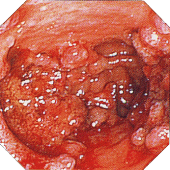

■活動期内視鏡的所見による分類

注12)内視鏡的に観察した範囲で最も所見の強いところで診断しする。 内視鏡検査は前処置なしで短時間で施行し、必ずしも全大腸を観察する必要はない。 棟方昭博:厚生省特定疾患難治性炎症性腸管障害調査研究班 平成9年度研究報告書